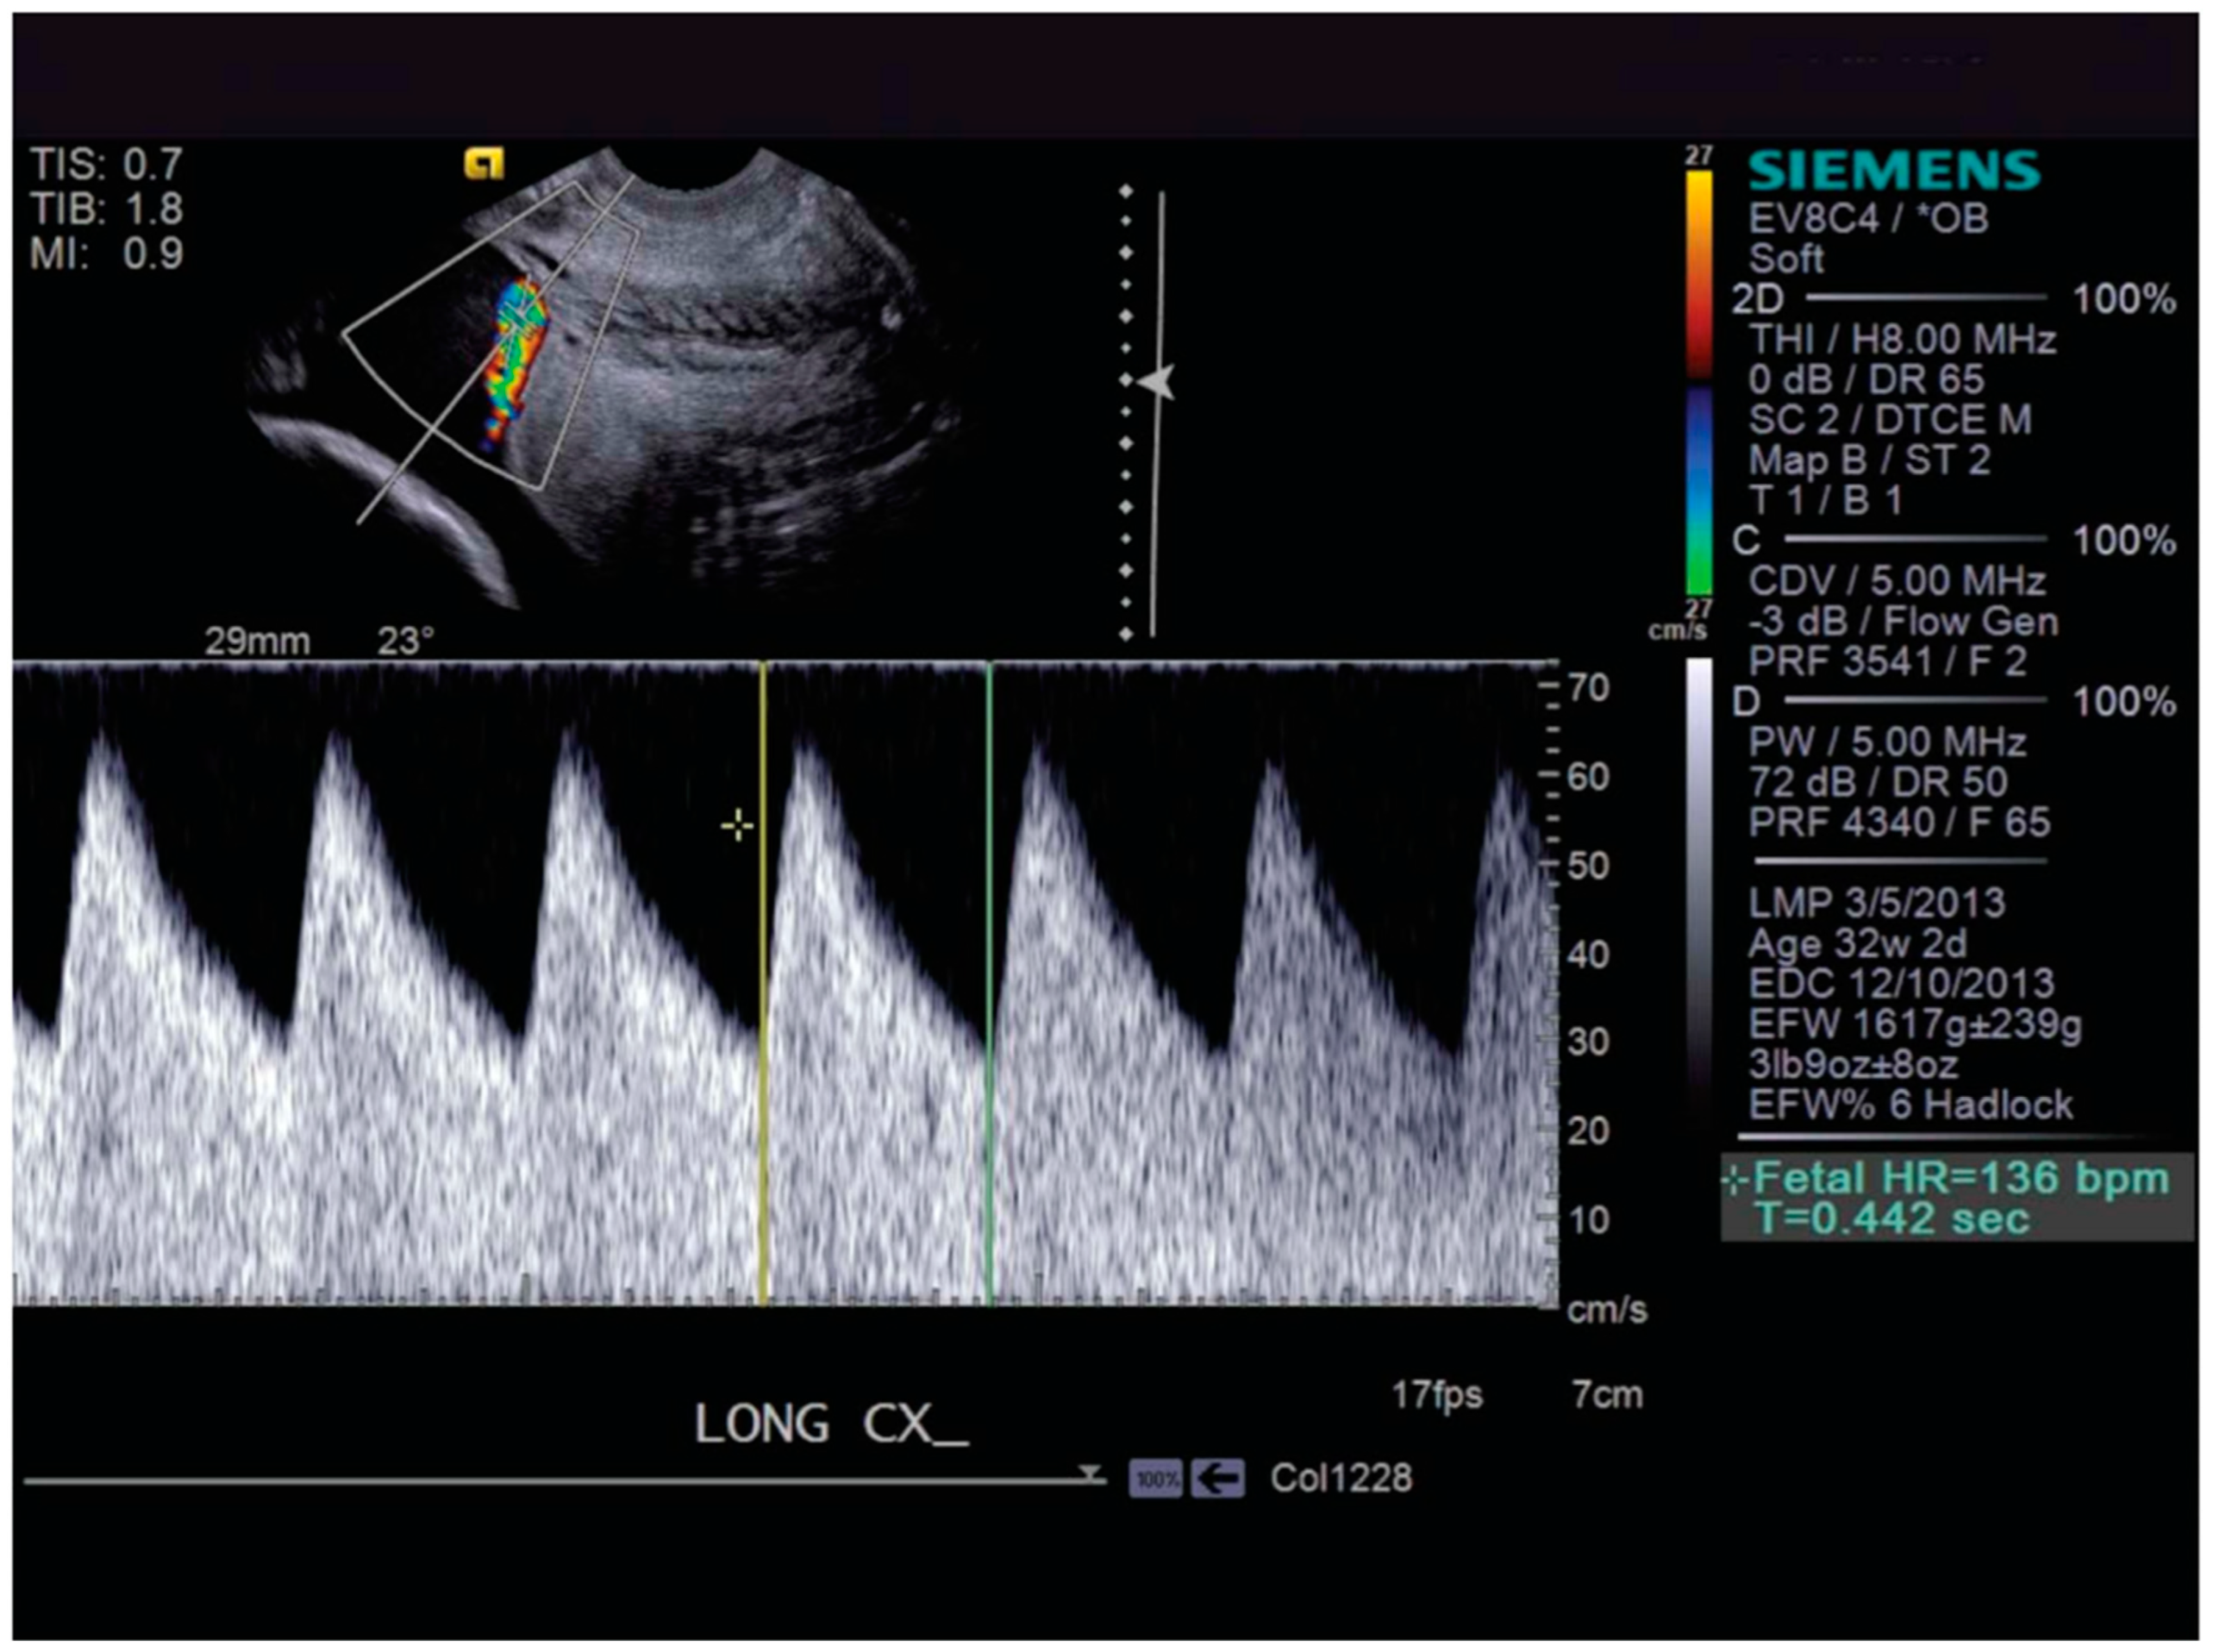

3.1. Vasa Previa: Definition and Diagnosis

5.1. What Is Cervical Length Surveillance and Why Is It Important?

5.2. Role of Cervical Length Surveillance in the Prevention of Preterm Birth